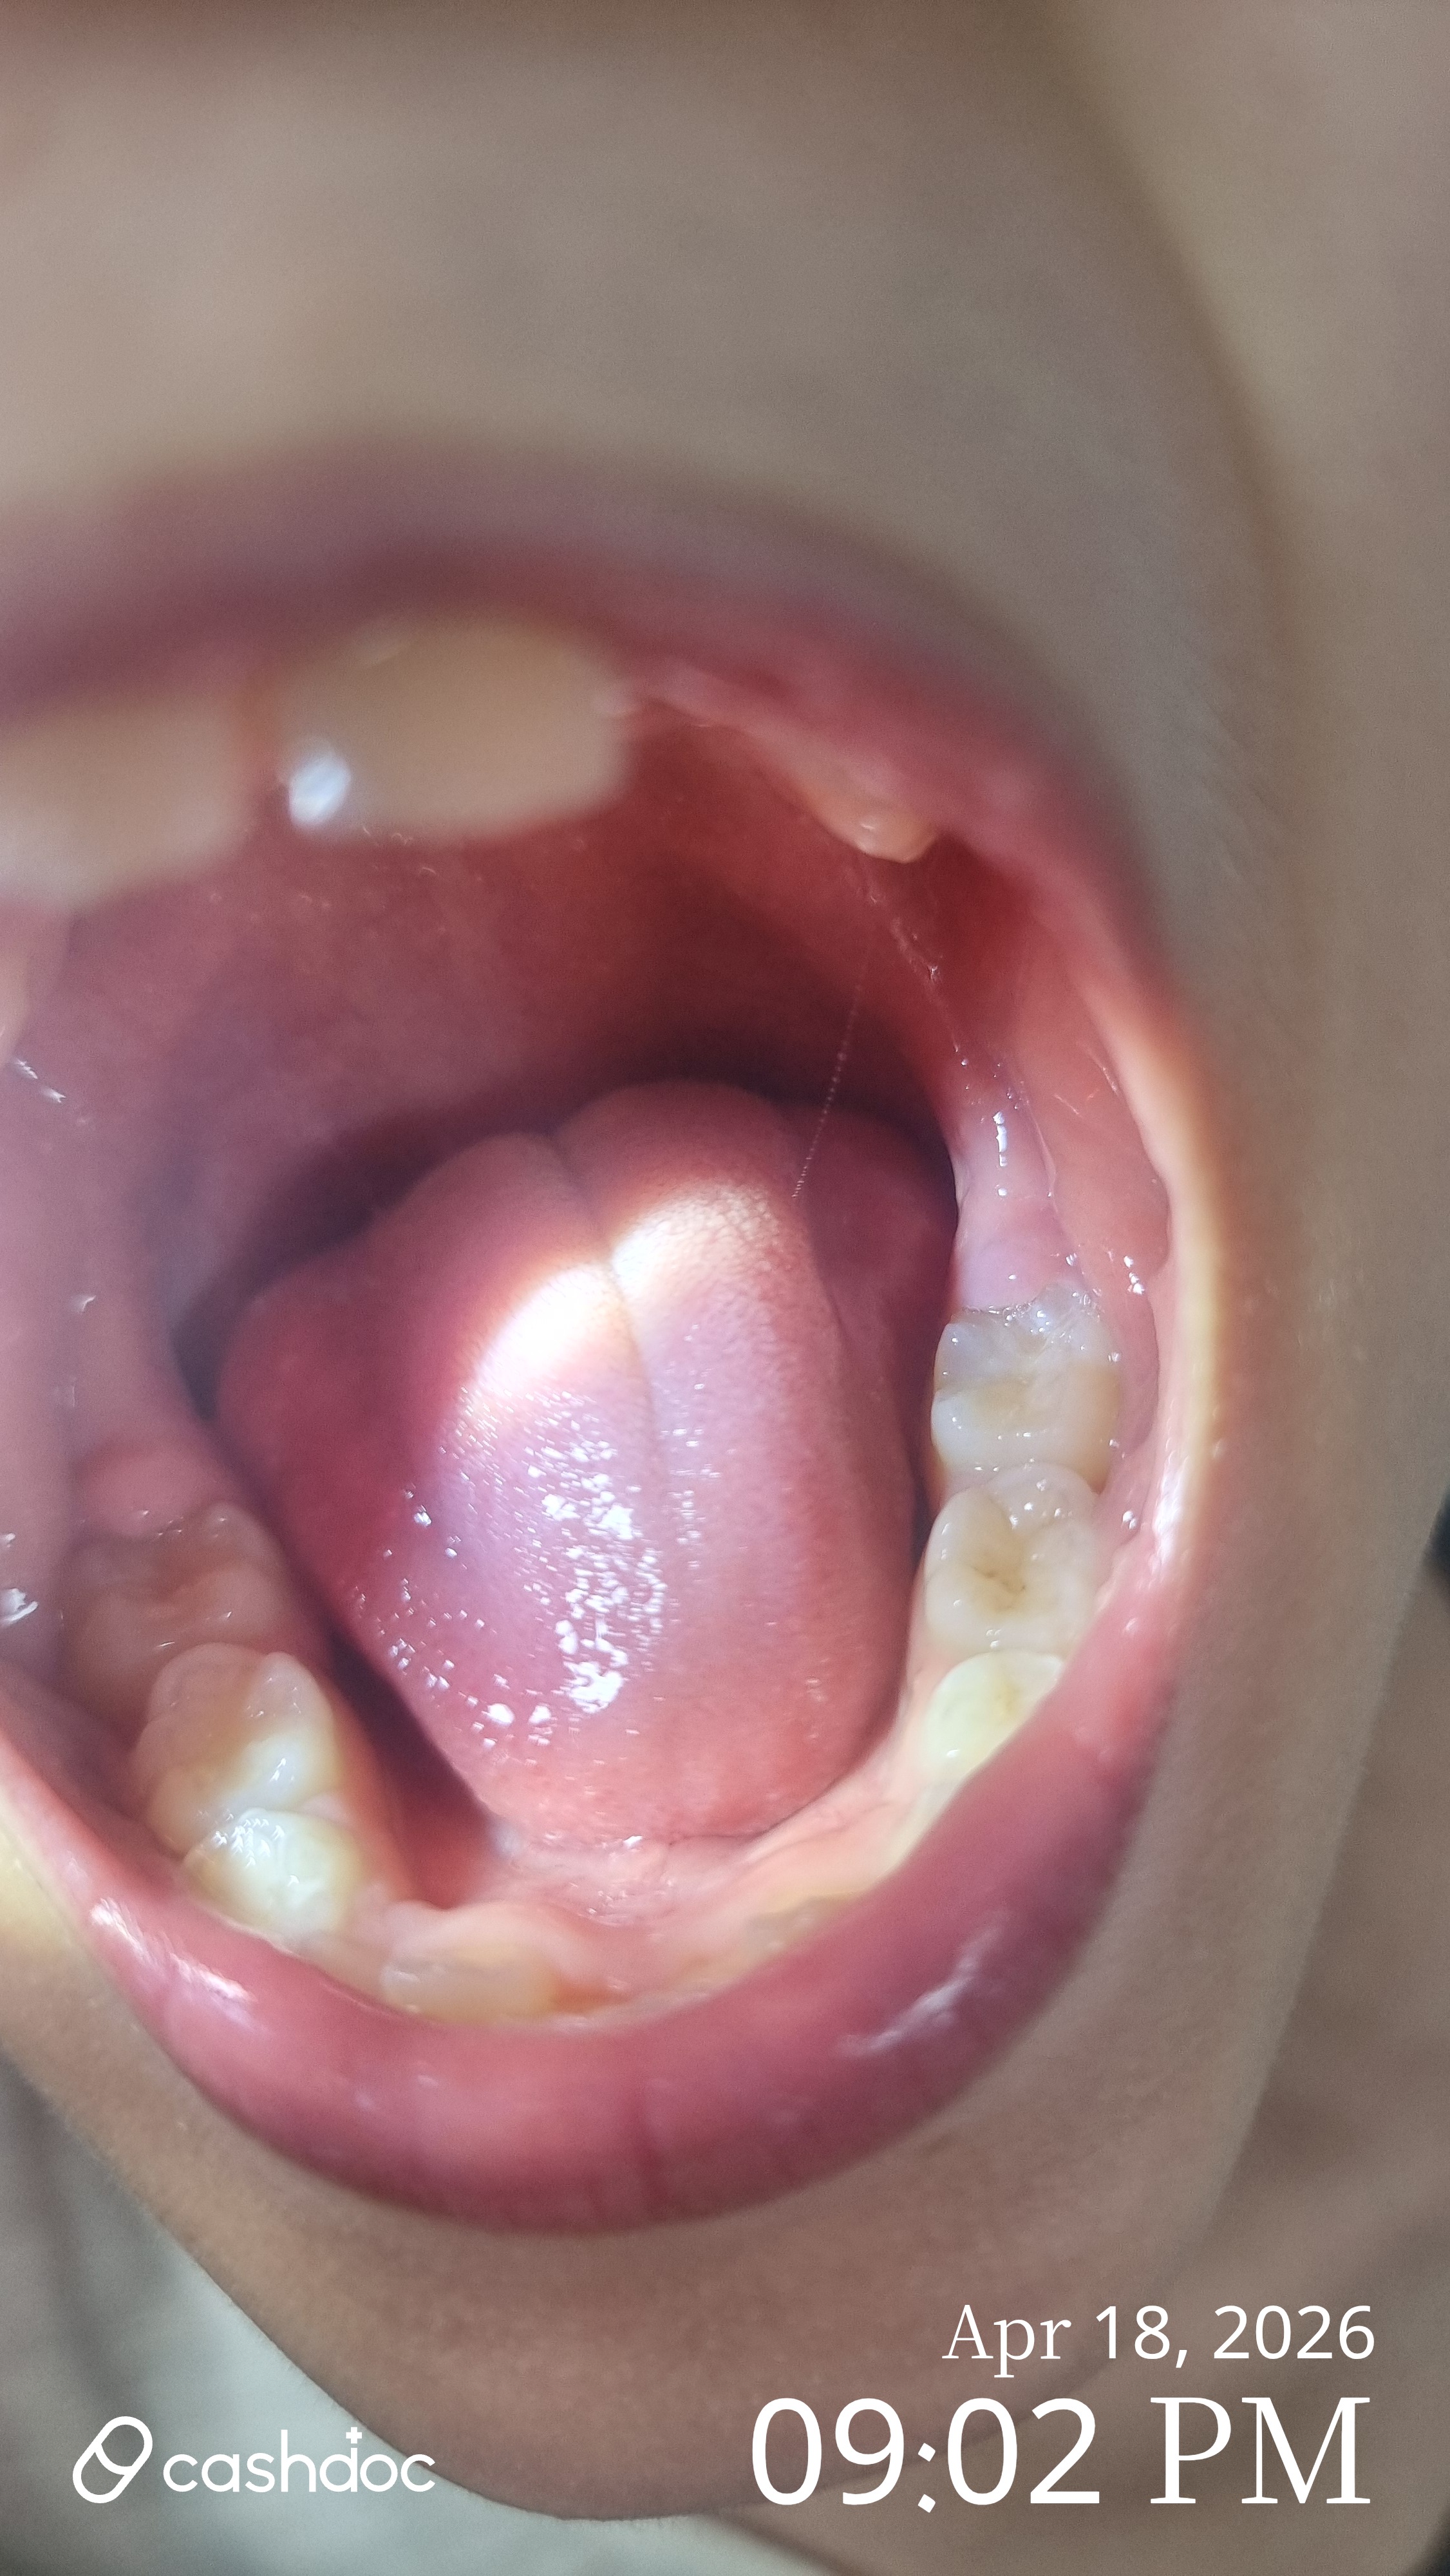

v 처음 가게 된 계기 : 가족들이 기존에 다니던 치과가 있었는데 아빠의 임플란트 치료를 위해 다른 치과 3군데를 상담하며 알아보다가 친절하고 꼼꼼한 상담, 진료로 만족해서 성심49플란트 치과의원으로 옮기게 되었어요. 성심49플란트 치과의원은 의사선생님들이 통합치의학과 전문의 2명, 치과보존과 1명 총 3분의 의사선생님이 임플란트, 교정과, 보철과, 충치 등 분야별로 나뉘어서 진료해주신다고 하기에 더 전문적인 느낌이여서 가게 되었어요. v 방문 전 걱정했던 점이나 망설였던 이유 : 나이가 들어가면서 치아도 노화를 느끼는 것 같아요. 잇몸이 약해진 것 같은 느낌과 치아 건강검진을 위해 방문하였는데 혹시나 충치나 신경치료 등 치아의 상태가 좋지 않아 치료를 해야 하는 상황이 될까 걱정이 되더라고요. v 실제 병원 분위기, 상담 과정, 설명은 어땠는지 : 성심49플란트 치과의원은 최신형 엑스레이 촬영을 하고 치아의 전반적인 상태를 꼼꼼히 모니터하고 치아상태에 대해서 이야기를 해주어요. 진료, 치료를 해주시는 의사쌤들도 분야별로 전문의들이고 친절하셔서 만족스러워요. 병원 의료진분들도 많고 상담도 상담간호사가 따로 해주고 꼼꼼히 안내해주고 상담해주어서 신뢰가 가는 곳이예요. (시술 전 찍어논 사진이 없어서..느낌만 보세요) (치아 노출 때운 후 제 사진) v 시술을 받았다면, 결정하게 된 이유 : 치과 정기검진으로 치과를 방문하게 되었고 스케일링을 받고 치아 아랫니 부분의 잇몸이 살짝 내려가서 아랫니 치아 1개가 뿌리부분이 살짝 노출이 되는 부분이 있었어요. 이렇게 되는 경우 지금 상태는 괜찮더라도 미관상에도 예쁘지 않기도 하지만 잇몸이 내려가면 치아의 신경이 자꾸 자극을 받게 되어 음식물을 섭취했을 때 치아가 시리거나 통증이 있을 수 있다고 했어요. 치아 때우기 시술은 시간도 오래 걸리지 않고 가격부담도 크지 않아서 치아 아랫니 부분을 레진으로 때우는 시술을 하기로 하였어요. v “처음이라서” 느꼈던 솔직한 감정들 : 치아치료는 충치, 신경치료, 임플란트만 생각했었는데 노화에 따라 잇몸도 내려가는 부분도 있어서 나이가 들수록 더 신경써야겠다는 생각이 들더라고요. 치아가 노출된 부분은 생각보다 빠르고, 티가 나지 않게 레진으로 때우기 때문에 간단한 시술이라고 생각했어요. 치아가 노출되지 않으니 더 깔끔해보이더라고요. v 다음에 다시 방문할 의사가 생겼는지 : 성심49플란트 치과의원은 치과 분야별로 세부화된 전문의들이 계시고 간호사, 병원 스텝분들도 많고 의사, 스텝분들이 다 친절하셔서 다시 방문하게 되더라고요. 그래서 온가족이 성심49플란트 치과의원로 옮겨 치과정기 검진과 다른 치과에 관한 치료도 성심49플란트 치과의원에 다니게 되었어요.